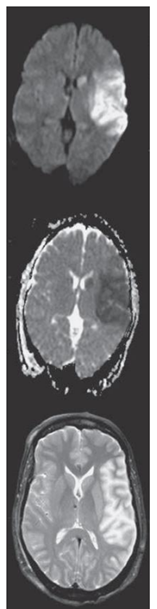

Observe a sequência de imagens Difusão, ADC e T2 em paciente

com Acidente Vascular Cerebral (AVC), adquiridas duas horas após

o evento.

A área afetada pelo AVC corresponde ao seguinte território vascular: